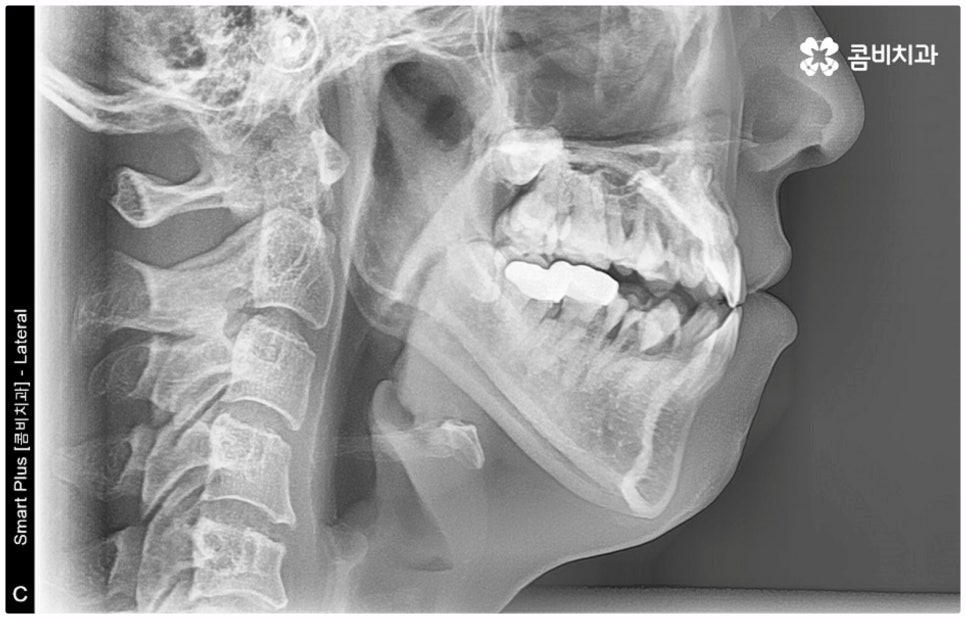

출처 아카이브 열기위아래 치열이 제대로 맞물리지 않으면 음식물을 씹을 때 어려움을 느끼거나 발음상 문제가 생길 수 있습니다. 이것을 부정교합이라고 하며, 그 종류는 상악과 하악의 골격적인 전후방 관계를 기준으로 1급, 2급, 3급으로 나눌 수 있어요. 위아래 어금니는 잘 맞물리는데 치열이 조금씩 삐뚤어져 있거나 치아 사이가 벌어져 있는 등 살짝씩 어긋난 부정교합은 1급, 위 어금니가 더 앞으로 나가있는 부정교합은 2급 (ex. 돌출입), 그리고 아래 어금니가 더 앞으로 나가있는 부정교합은 3급 (ex. 주걱턱) 으로 분류하게 되는데 이 중 오늘 살펴보려고 하는 것은 부정교합 3급에 해당하는 반대교합에 대한 거예요.

정상적인 교합은 윗 앞니가 아래 앞니를 살짝 덮는 정도로 윗니가 조금 더 앞으로 나와 있으면서 위아래 치아가 어금니까지 잘 맞물리는 것을 말하는데 반대교합은 위아래 앞니가 거꾸로 물리는 증상을 보이기 때문에 저작 활동 및 발음 조성이 원활하지 않게 되며 반대교합교정 등 적절한 치료를 받지 않고 방치할 경우 점점 더 주걱턱이 강화되는 쪽으로 뼈가 성장할 수 있어 될 수 있는 대로 빠른 시일 내에 원인을 분명하게 알아보고 그에 맞는 치료를 받는 것이 중요하다고 할 수 있어요.

골격적인 원인으로 인한 것이라면 반대교합교정 치료를 할 때 위턱의 성장을 유도하고 상대적으로 아래턱 성장을 저지하는 방향으로 상악과 하악의 위치 관계를 개선하는 방법을 사용하게 되며 환자분들의 상황에 따라 악궁확장장치 또는 페이스마스크 등의 장치를 이용하게 되는데, 이렇게 골격적인 부분에 크게 영향을 받은 경우 재발의 가능성 역시 높기 때문에 어릴 때 교정 치료를 시작하여 치열이 고르게 돌아왔다고 해도 성장이 완료되는 시기까지 꾸준하게 관리를 해 줄 필요가 있어요.

반대교합의 경우 보통 두 원인이 혼재되어 나타나는 경우가 많으며 또한 환자분들의 상황에 따라 정확한 치료가 달라지기 때문에 꼼꼼한 검진 후 각자에 맞는 반대교합교정 치료를 통해 이를 바로잡아 주시길 권유드리고 있어요. 검진과 치료를 받을 때는 3D CT와 같은 정밀 검사 기계를 갖추고 있는 치과에서 임상 경험이 풍부하고 뛰어난 노하우와 기술을 가지고 있는 숙련된 의료진에게 반대교합교정 치료를 진행하는 것이 좋을 거예요.